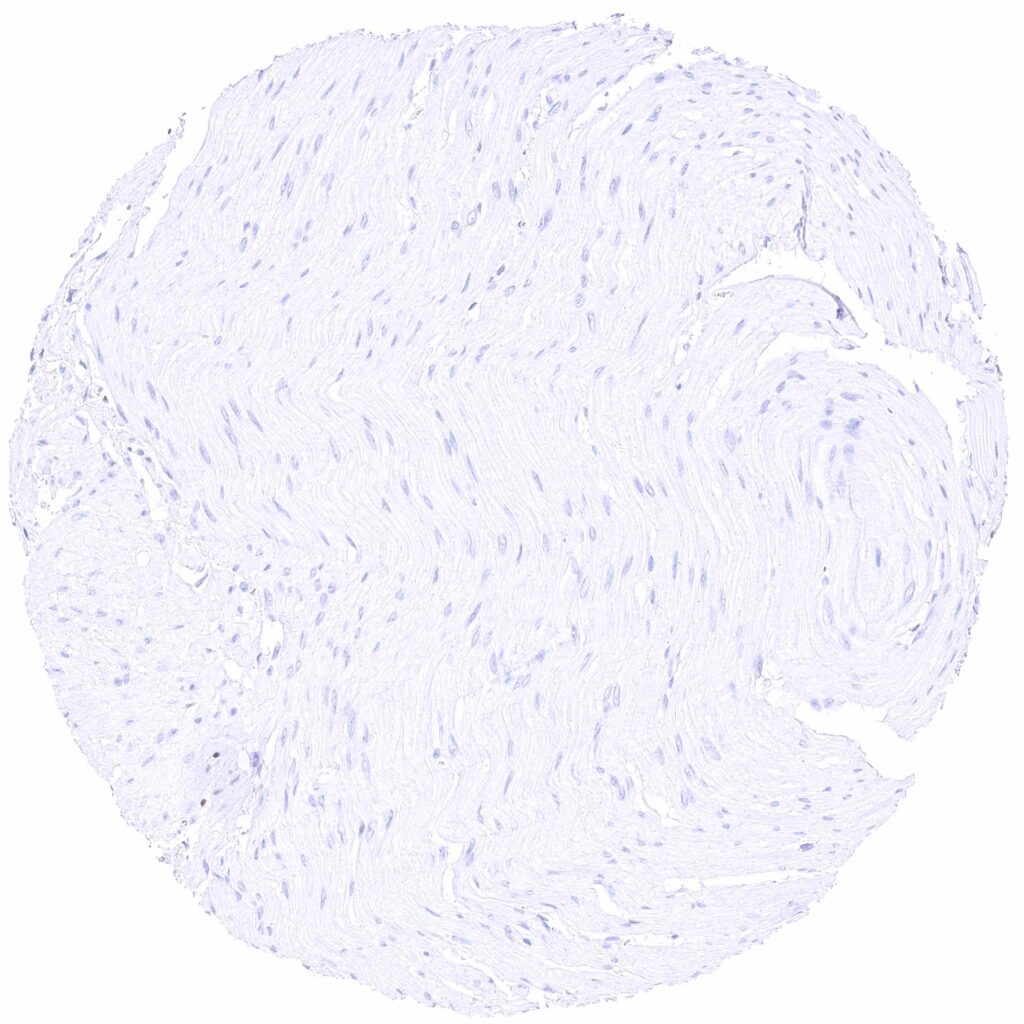

Esophagus, muscular wall

Heart muscle

Skeletal muscle

Urinary bladder, muscular wall

Uterus, myometrium